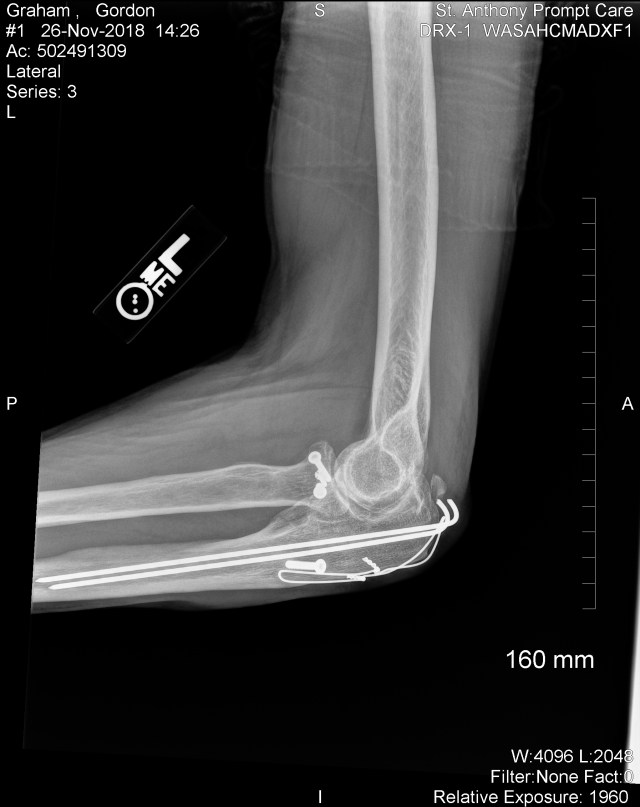

Brand new bone chip @ L elbow 11/18/2018.